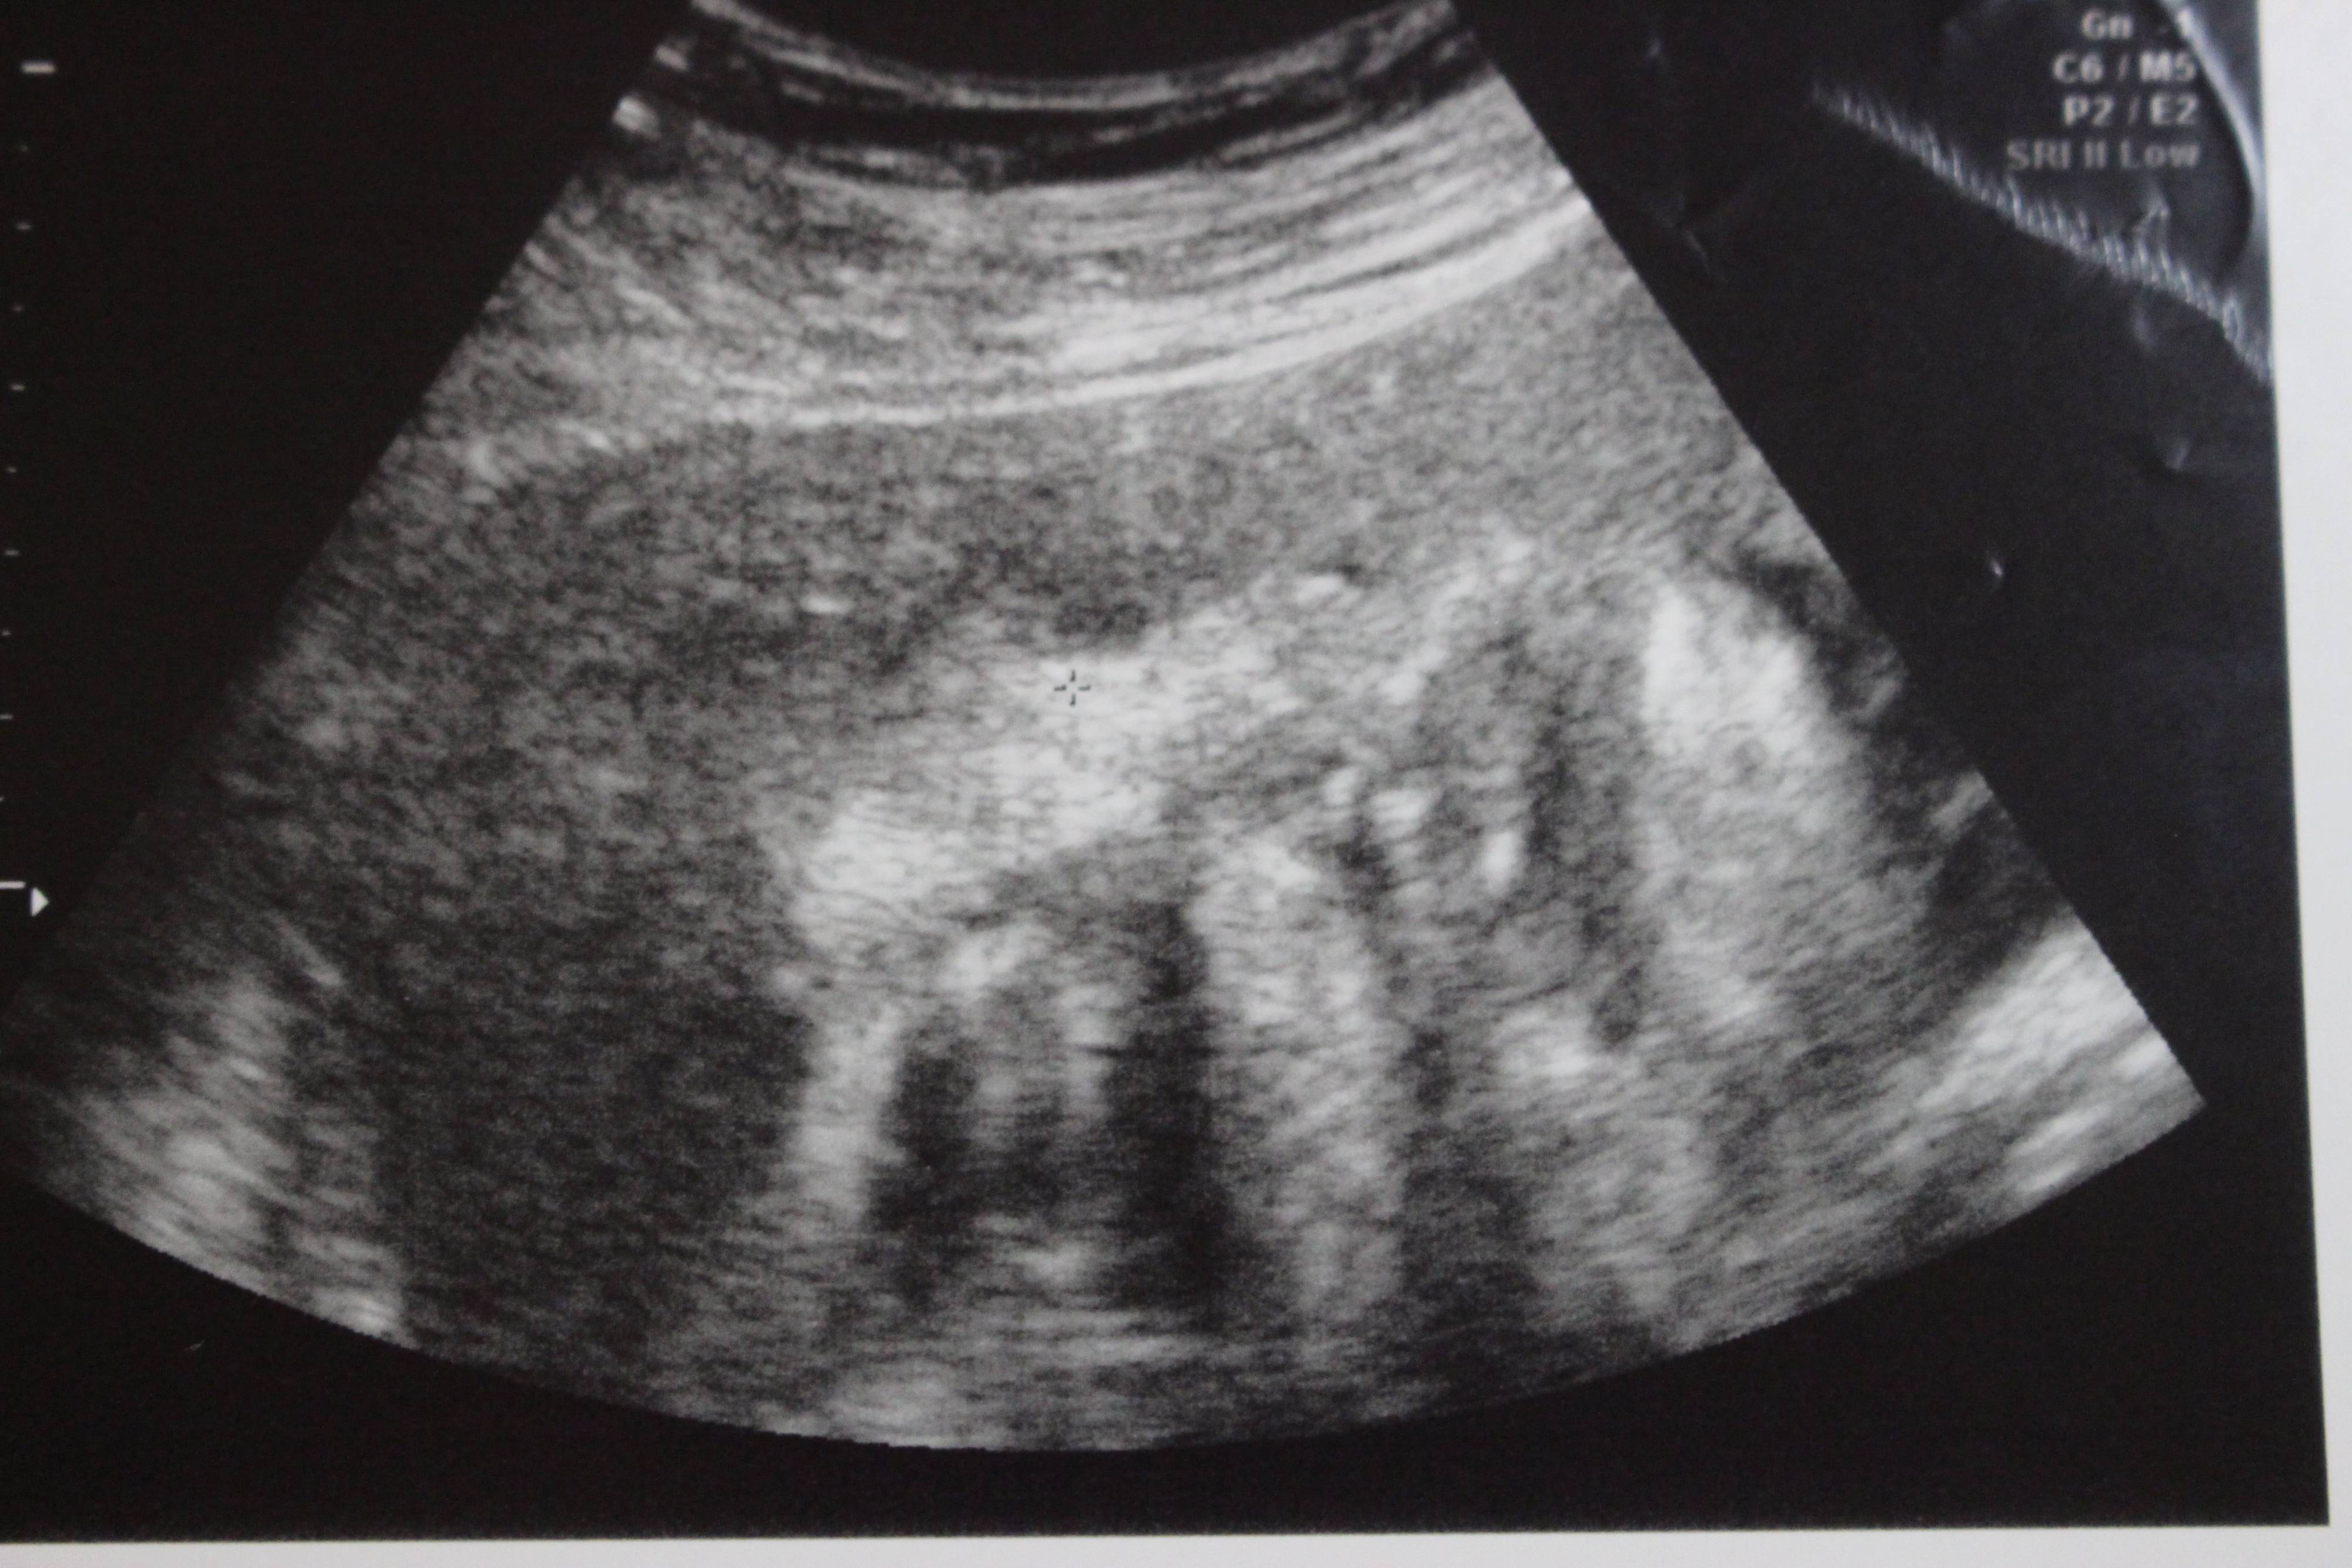

妊娠33週目のエコー写真

「顔上向き、黒いところは目。2200g~2300g」と記してあります。右上にある黒い丸2つが目でその間に鼻がうつっています。口を開けているところ?このころは、おなかが大きくなり自分で足の爪を切ることが難しかったので、看護師さんにお願いしていました。